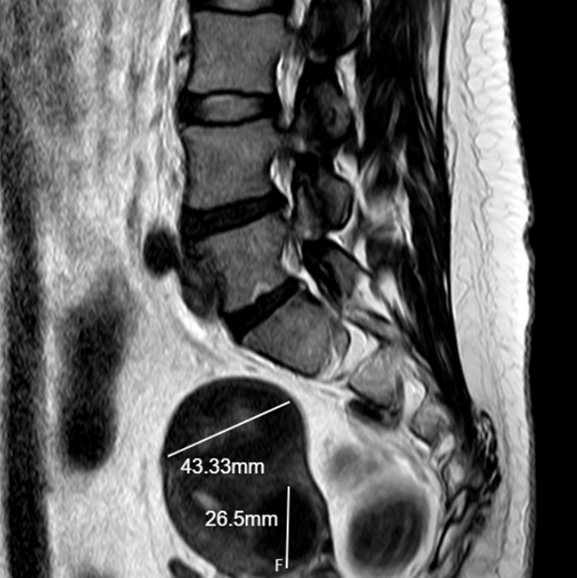

왼쪽 윗배(좌상복부)에는 비장(지라), 췌장(일부), 위, 신장, 좌측 폐 하부, 대장(비장만곡) 등 여러 장기가 밀집해 있어 정확한 진단 없이는 원인을 쉽게 알기 어렵고, 치료 시기를 놓치면 내출혈, 췌장염 악화, 장기 파열 같은 심각한 상황으로 번질 수 있습니다.